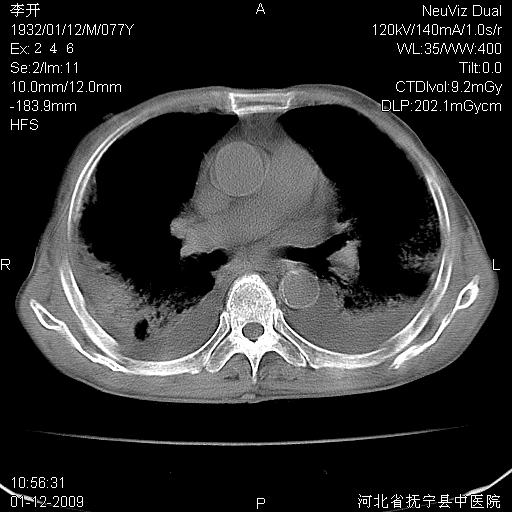

以下是引用黑白光影在2009-1-19 16:49:00的发言:[br]心衰肺水肿;心包、胸腔积液;冠脉钙化;肺部感染。